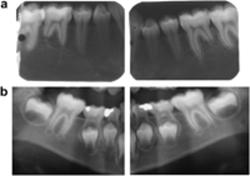

Resorption of the permanent teeth was seen in four subjects. These resorptions were as follows: ongoing idiopathic external apical resorption of the mandibular first molars with the most pronounced resorption of the distal roots, seen in one patient who had not received orthodontic treatment (Figure 4); one case of internal crown resorption of a permanent molar; external apical resorption of molars, incisors, and lower canines, seen in two subjects who had received orthodontic treatment (Figure 5).

View larger version:

Figure 4

(a) Dental pantomogram (DPT) of the permanent mandibular regions of a girl aged 15 years 11 months showing short roots of the permanent mandibular first molars. The girl had not received orthodontic treatment. (b) For comparison of the mandibular regions (shown in (a)), two segments of the DPT of the early mixed dentition taken 9 years 5 months earlier of the same girl are shown. The root length of the first permanent molar appears longer than shown in (a), and accordingly an unexpected root resorption of the permanent mandibular molars has occurred. Unexpected early apical resorption of primary mandibular molars is also seen in (b).

Figure 5

(a) Dental pantomogram (DPT) of the permanent dentition of a boy aged 17 years 5 months with invaginations of the lateral incisors and short roots of mandibular molars. (b) For comparison of the mandibular regions (shown in (a)), two segments of a DPT of the same boy taken 9 years 3 months earlier are shown. Root resorption of the permanent mandibular molars has occurred since the DPT shown in (a) was taken. The patient has received orthodontic treatment. Note less severe early apical resorption of the primary teeth.